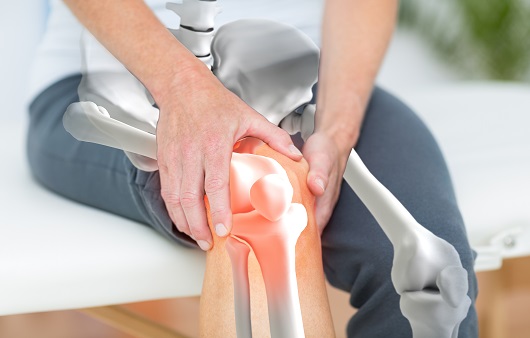

사람들이 나이가 들어감에 따라 자연적으로 관절이 안 좋아지는데요. 우리나라 성인의 만성질환 1위가 관절염이라고 하니 관절염으로 인한 통증으로 많이 불편해 하는 현실입니다. 관절염 통증은 많은 이유가 있겠지만 관절 사이에서 완충 작용을 하는 연골이 닳아서 충돌하면서 발생하는 경우가 많습니다. 이 연골의 주 성분이 콘드로이친 이라는 성분인데요.이 성분이 떨어지면 각종 관절염, 근육통 등 증상이 발생하게 됩니다. 콘드로이친은 우리 몸에서 스스로 생성되지 않는 성분으로 꼭 섭취를 통해서만 보충이 가능하다고 하네요.

최근에는 콘드로이친이라는 물질이 뜨고 있는데 그리스어로 연골이라는 의미의 콘드로이친은 상어와 소 연골에서 추출되는데 이는 관절끼리 부딪혀 마모되는 것을 막아주고 동시에 충격을 흡수하여 자유롭게 움직일 수 있도록 도와주어 건강 기능 식품으로 떠오르는 물질입니다.

콘드로이친의 가장 큰 효능은 바로 연골 감소 예방입니다. 콘드로이친은 연골에 영양분을 공급하는 역할을 합니다. 연골에 충분한 영양분들 공급하여 연골의 탄력과 힘을 보충하여 연골이 마모되는 것을 예방해 줍니다. 한 실험울 통해서 콘드로이친을 일정하게 섭취한 사람과 아닌 사람의 연골 마모 속도가 2배 이상 차이가 난다는 결과가 있습니다.

관절 속 충격완화 및 충격을 방지하는 역할을 하는 콘드로이친 성분으로 하여금 연골 형태 및 탄력을 유지시킴으로 통증은 완화시키고 염증은 억제하는데 도움이 됩니다. 연구 결과 통증 완화 감소 정도가 소염진통제 만큼 뛰어난 것으로 알려져 있습니다.